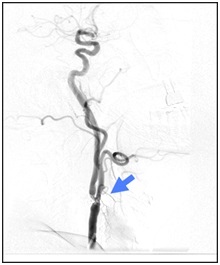

Los objetivos de la prevención son limitar la progresión de la aterosclerosis y reducir el riesgo de ACV y otros sucesos vasculares (4). De este modo, las indicaciones para la revascularización dependen sobre todo del grado de la estenosis y de si el paciente ha experimentado recientemente síntomas neurológicos (5). La Figura 1 muestra una imagen radiológica de un paciente afecto de estenosis carotídea.

Fig. 1: Imagen radiológica de estenosis carotídea.